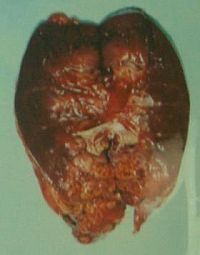

先ず取り出した腎臓はその場で執刀医に2枚におろされ、開きにされます。(左写真マウスを重ねると拡大します)

この時点で、執刀医には外観で癌の種類は大抵分かるそうです。

しかし、まだ確定ではありません。

この後、病理医に回され、病理検査で確定します。